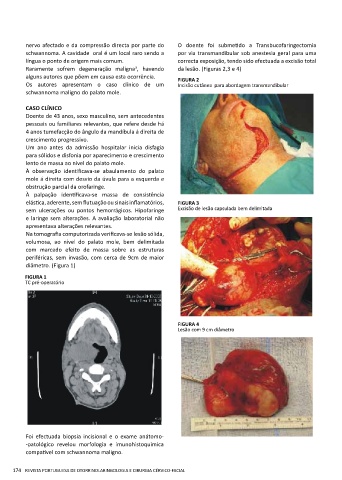

alguns autores que põem em causa esta ocorrência. FIGURA 2

Os autores apresentam o caso clínico de um Incisão cutânea para abordagem transmandibular

elástica, aderente, sem flutuação ou sinais inflamatórios, FIGURA 3

sem ulcerações ou pontos hemorrágicos. Hipofaringe Excisão de lesão capsulada bem delimitada

FIGURA 4

Lesão com 9 cm diâmetro